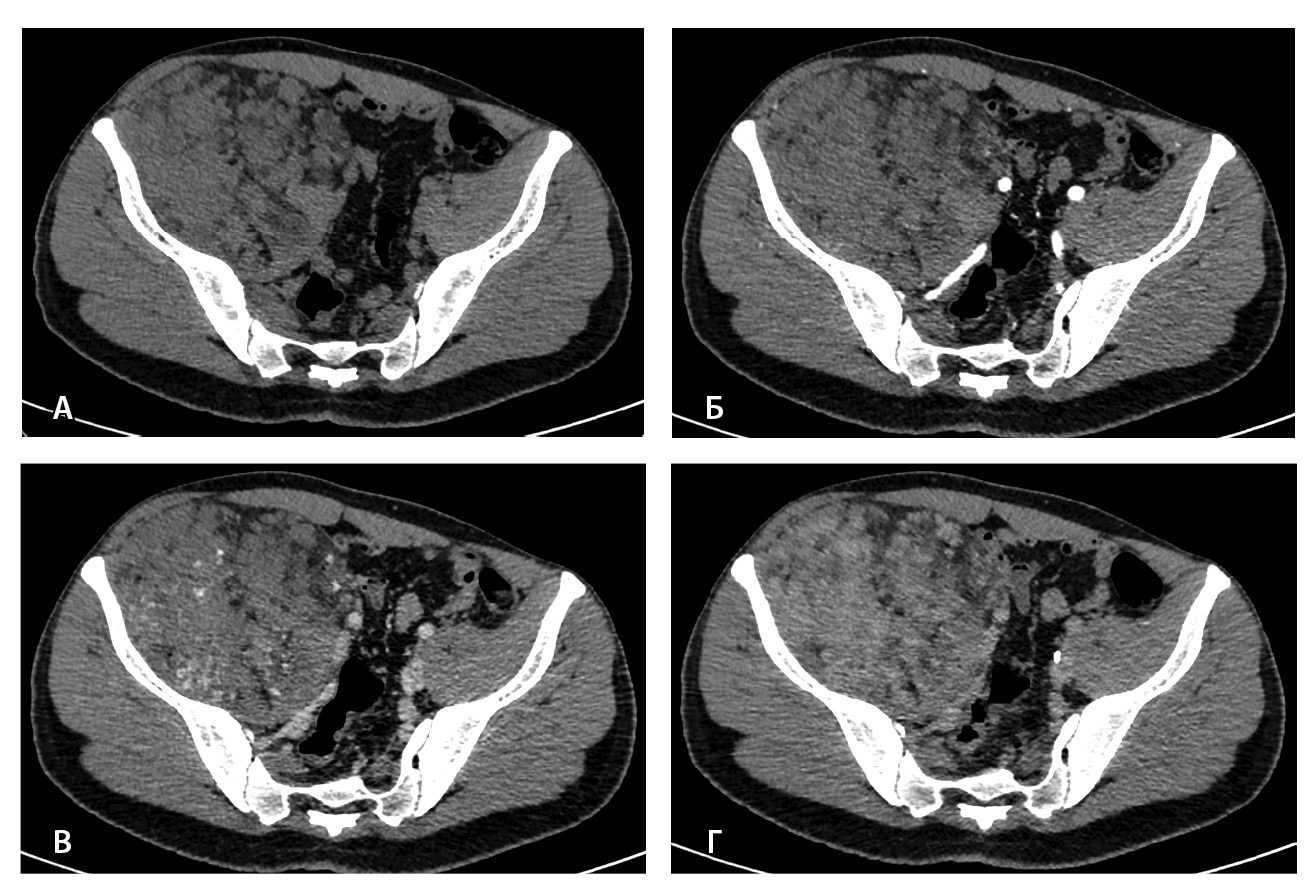

Результаты дооперационной мультиспиральной компьютерной томографии органов брюшной полости и забрюшинного пространства (рис. 1, 2): «В забрюшинном пространстве справа визуализируется образование, исходящее из подвздошно-поясничной мышцы, с выходом вдоль сосудистого пучка на верхнюю треть бедра. Образование с четкими и ровными контурами, размерами 145 × 125 × 125 мм. Структура образования гетерогенная, плотность в нативную фазу исследования от –40 до 50 HU, содержит единичные кальцинаты, жировую ткань и мягкотканный компонент. На фоне контрастирования в артериальную и венозную фазы в структуре выявляются извитой формы участки гиперконтрастирования (сосудистая сеть). Максимальное накопление контрастного препарата происходит преимущественно к отсроченной фазе исследования. Усредненные плотностные характеристики составляют 25, 36, 53 и 59 HU в нативную, артериальную, венозную и отсроченную фазы соответственно. Опухоль оттесняет тазовую брюшину, правую подвздошно-поясничную мышцу, илеоцекальный угол кпереди. Образование тесно прилежит сзади к крылу правой подвздошной кости и лобковой кости, спереди – к прямой и внутренней косым мышцам живота, верхним контуром – к поясничной мышце. Медиально в средней трети по контуру образования проходят правые наружные и внутренние подвздошные сосуды, со сдавлением наружной подвздошной вены. Данных за распространение на прилежащие внутренние органы и клетчатку не получено. Кости без деструктивных изменений».

Рис. 1. Мультиспиральная компьютерная томография органов брюшной полости и забрюшинного пространства с болюсным внутривенным контрастированием: А – нативная фаза, Б – артериальная фаза, В – венозная фаза, Г – отсроченная фаза. Крупное гетерогенной структуры образование забрюшинного пространства справа, с фокусами гиперваскуляризации в структуре. Тесно прилежит к крылу подвздошной кости и подвздошным сосудам, оттесняя последние медиально